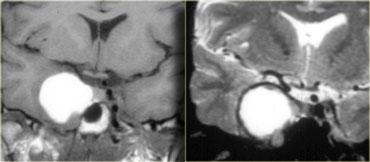

Sọ hầu u (Craniopharyngioma)

Sọ hầu u là bệnh lý thứ ba trong số ba bệnh lý có nguồn gốc từ biểu mô khe Rathke.

Về mặt kỹ thuật, đây là các khối u lành tính, nhưng khác với nang khe Rathke, chúng có thành dày và xâm lấn tại chỗ.

Về đại thể, đây là một khối phức tạp với nhiều nốt ở nền não, len lỏi dọc theo các khe não.

Thông thường, khối u không thể được cắt bỏ hoàn toàn.

Hình ảnh bên phải cho thấy một nang thành dày là một phần của sọ hầu u.

Trong hơn 50% trường hợp, sọ hầu u có hình ảnh đặc trưng bệnh lý (pathognomonic).

Trên các hình ảnh chuỗi xung T1W mặt phẳng đứng dọc không và có tiêm thuốc tương phản từ, có thể nhận thấy tuyến yên bị chèn ép.

Có một khối lớn trong hố yên và trên hố yên với các thành phần dạng nang, thành phần ngấm thuốc cũng như vôi hóa.

Các dấu hiệu này ở trẻ em gần như là đặc trưng bệnh lý của sọ hầu u (có thể chỉ cần chẩn đoán phân biệt với u bì – dermoid).

Hình ảnh mặt phẳng đứng ngang (coronal) của cùng một khối.